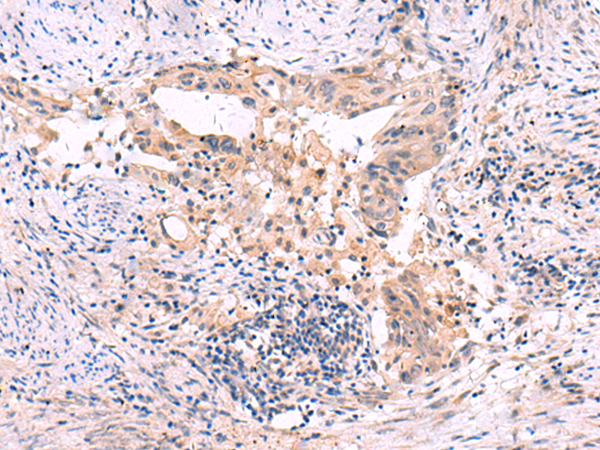

IHC positive control: |

Human cervical cancer |

IHC Recommend dilution: |

30-150 |